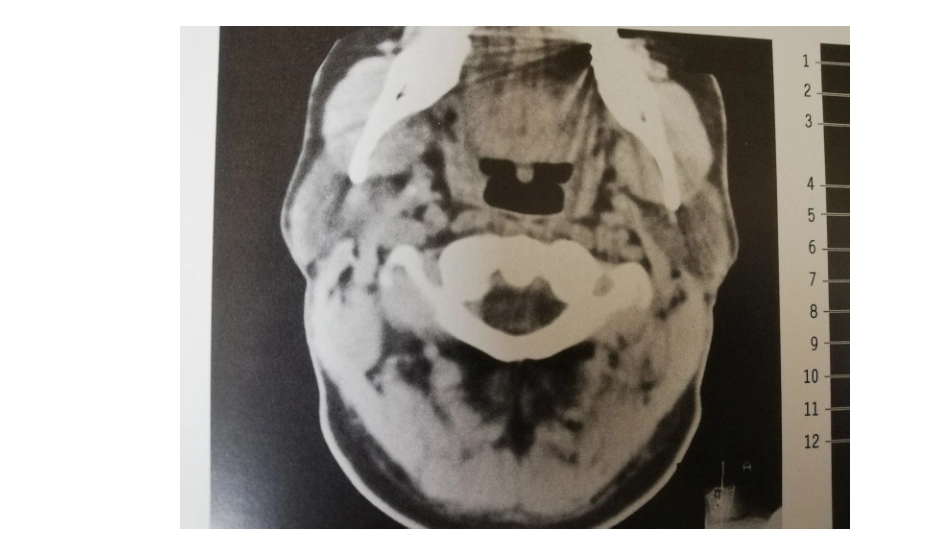

颈部正常轴位CT寰椎(悬雍垂)层面C2、C3层面(会厌上缘及以上)舌骨及会厌前间隙(C4)甲状软骨上切迹至声门声门下甲状腺中下部胸膜顶及稍下胸骨上切迹谢谢聆听

颈部正常轴位CT解剖图解